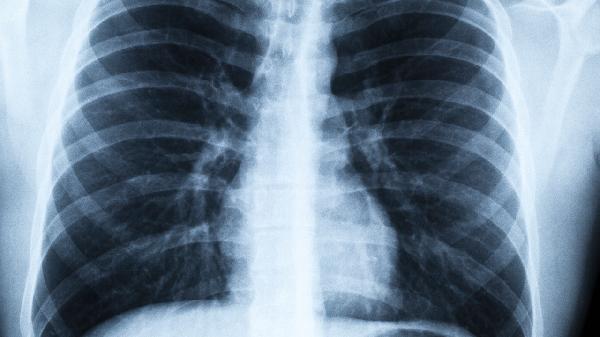

病毒性肺炎口服藥吃什么比較好用

關(guān)鍵詞: #肺炎 #病毒

病毒性肺炎常用口服藥物包括奧司他韋、阿比多爾和法匹拉韋,具體用藥需根據(jù)病原體類型和醫(yī)生指導選擇。病毒性肺炎的治療藥物主要有抗病毒藥物、免疫調(diào)節(jié)劑、止咳化痰藥、解熱鎮(zhèn)痛藥和中藥制劑。